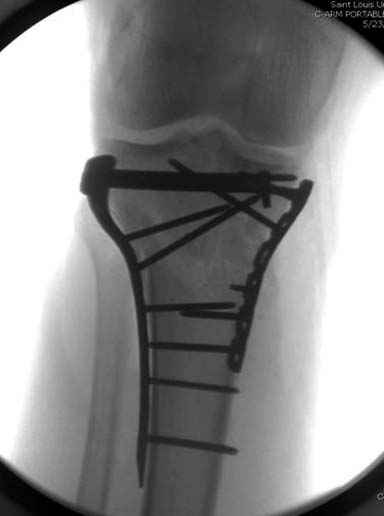

Решили выполнить остеосинтез штифтом и внутрисуставного перелома пластиной и винтами. Жду мнения! Зачем мне оправдываться-я же не преступник. Диалогом называется...

Отдельные переломы тибиал плато и перелом проксимальной трети большеберцовой кости отличаются от переломов тибиал плато с вовлечением диафиза. Здесь перелом тибиал плато типа Schatzker VI, полученный в результате высокоэнергетической травмы. Перелом метафиза образовал отрыв суставной поверхности от диафиза с вовлечением медиального и латерального мыщелков. Двухмыщелковые переломы из-за укрочения опасны развитием компартаментального синдрома, повреждением латерального мениска и связок.

При переломах одного из мыщелков тибиал плато+дополнительный перелом проксимальной трети большеберцовой кости можно применить комбинированный вариант фиксации, т.е. мыщелок винтами или пластиной, а для диафиза можно установить гвоздь. В данном варианте потеряно преимущество гвоздя , из-за серьезной травмы суставной поверхности нельзя нагружать ногу несколько месяцев. А без нагрузки гвоздь просто заполнитель пространства внутри кости!

На вашем место я бы подождал с фиксацией до готовности кожных покровов, и за это время можно было подобрать соответствующий фиксатор, т.е более длинная пластина снаружи и медиальная пластина на апексе перелома как подпорка. Здесь приемлем как раз минимальный доступ.

Имеющаяся импрессия не потребовала пластики - достаточным оказалось поднять отломок

Если там действительная импрессия, пустое место без структуральных заполнителей, кость или синтетические материалы, не восстановится, а образуется коллапс, и ось конечности поведет после нагрузки. Кроме того там возможно "болт стяжка"?, в медиальной стороне выступает за кортекс, можно было укоротить! Потом создается впечатление, что не соответствуют мыщелки большеберцовой и бедренной костей? Покажите снимок.

Ваша упорство с минимальными данными защищаться забавляет, и пока не все убедились в Вашей правоте. Для нормальной защиты необходимы аргументированные доказательства исследованиями. КТ сканы и прицельно сделанные снимки коленного сустава, а так все аргументы - не более чем "моя фиксация, мне нравится". Без этих доказательств пока только Ваше упорство.....

Здесь пару случаев для сравнения,...в первых 1-4 слайдах метод фиксации одним фиксатором, как видно после 8 месяцев сохранилась ось. С 5 по 9 вариант двумя пластинами...